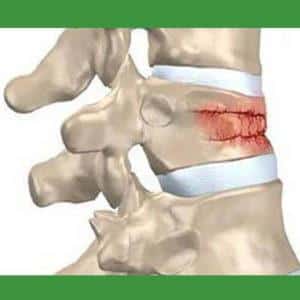

- переломы позвонков: компрессионные, оскольчатые, краевые, взрывные, вертикальные и горизонтальные;

Ушибы и сдавливание часто возникают в результате травм позвоночника, таких как вывихи или переломы. При ушибе происходит нарушение целостности спинномозговой ткани, что приводит к образованию кровоизлияний и отека, степень которых зависит от тяжести повреждения.

Сдавливание возникает при переломах тел позвонков и может быть как частичным, так и полным. Часто сдавливание наблюдается у ныряльщиков, при этом наиболее уязвимыми являются нижние шейные позвонки.